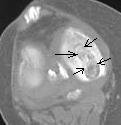

А вот примерно так выглядит это ложе на КТ, пока оно ещё не опустело (ложе в медиальном мыщелке помечено стрелками). Б-нь Кенига.

Конечно, Валентин Львович, я не обратил внимание на существование сайта, теперь добавлю туда несколько КТ-картинок.